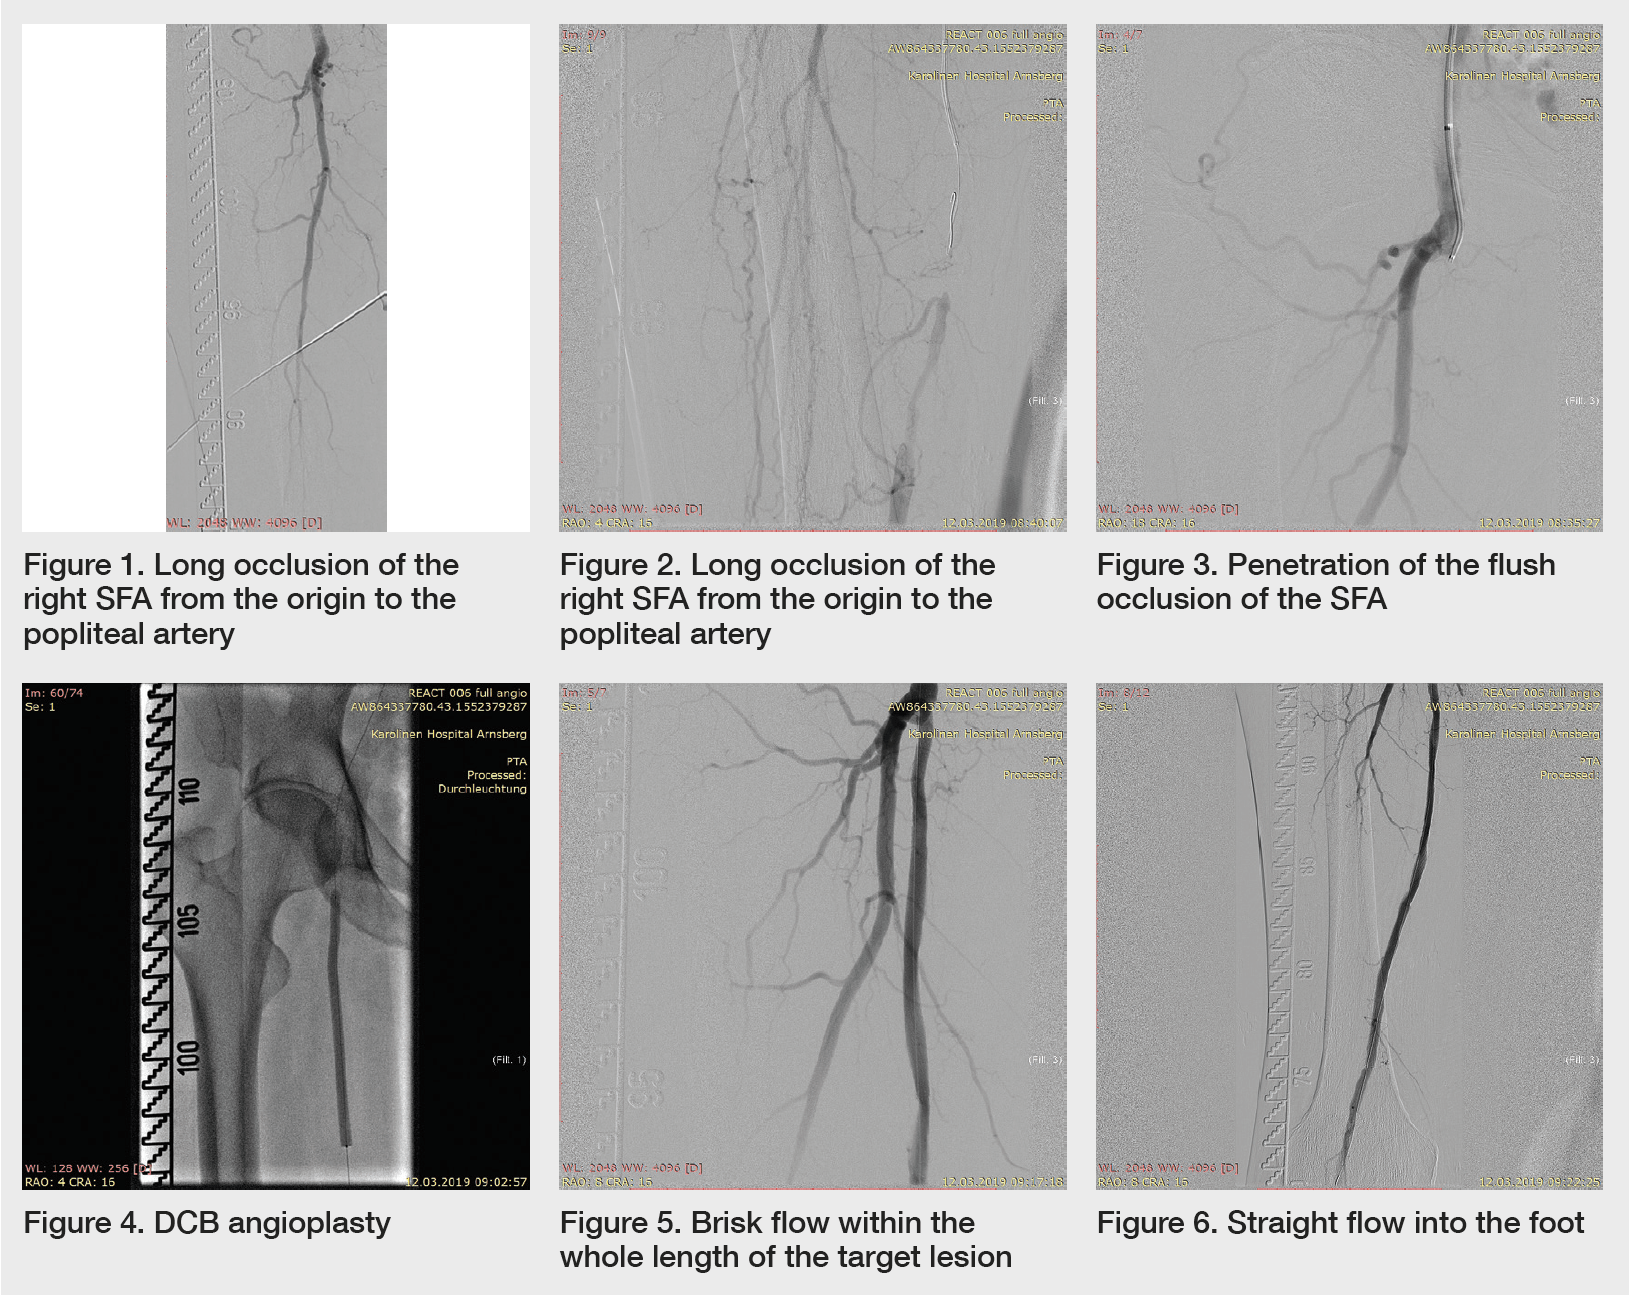

Subintimal angioplasty of a flush occlusion of the superficial femoral What Is Occlusion Of Sfa Distinct sfa stenoses or occlusion on the final arteriogram (n = 98) were characterized by their location, length, stenosis severity, and morphologic appearance on the initial. Angiograms highlighting the long sfa. Treatment of the superficial femoral artery (sfa) has been among the least effective of all endovascular procedures in terms of long. The ongoing left sfa was occluded, with reconstitution. What Is Occlusion Of Sfa.